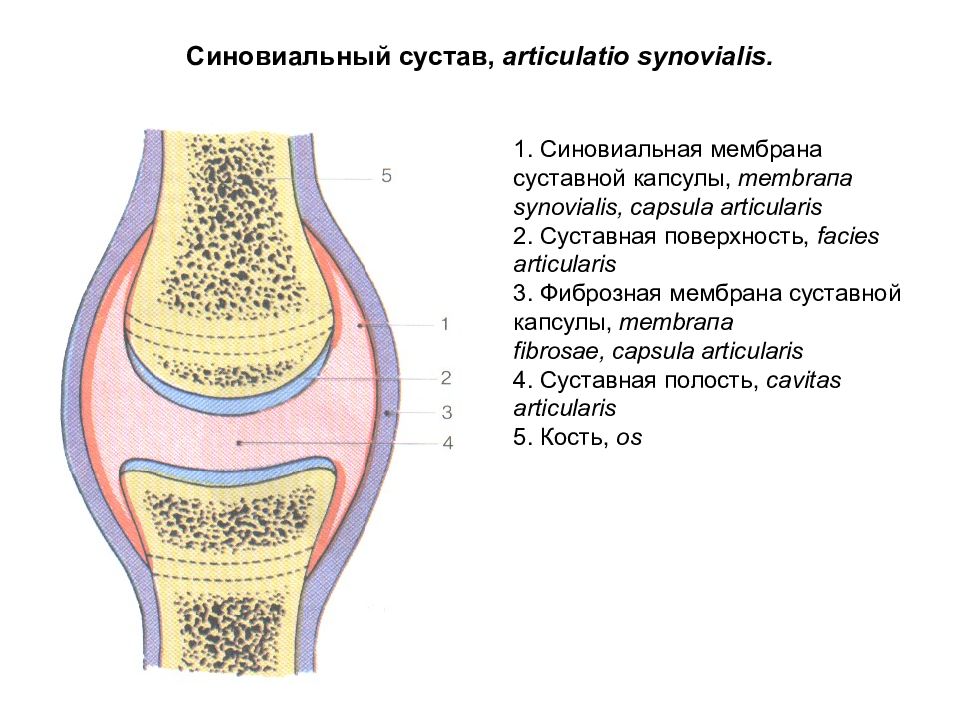

Рисунки Суставов: Анатомические Иллюстрации